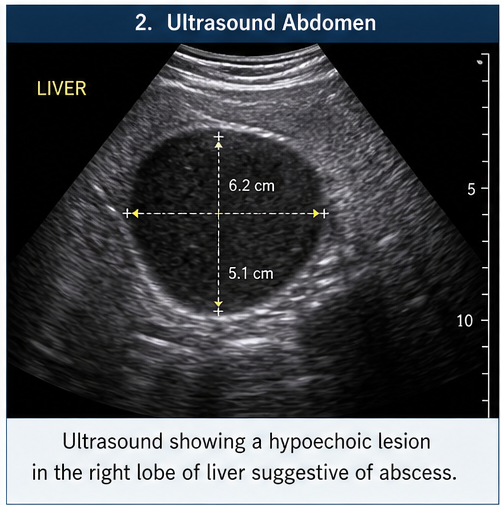

Ultrasound Abdomen

Findings were consistent with amoebic liver abscess.

A diagnosis of amoebic liver abscess secondary to Amoebiasis was established based on a comprehensive correlation of clinical, radiological, and laboratory findings. The patient’s presentation with fever, right upper quadrant pain, and gastrointestinal symptoms, along with epidemiological risk factors such as exposure to contaminated food and water, raised a strong initial suspicion. Imaging studies, including ultrasound and contrast-enhanced CT, demonstrated a characteristic hepatic abscess with supportive features. This was further substantiated by positive serological testing for Entamoeba histolytica infection antibodies, thereby confirming the diagnosis and excluding other potential differentials such as pyogenic abscess or malignancy.